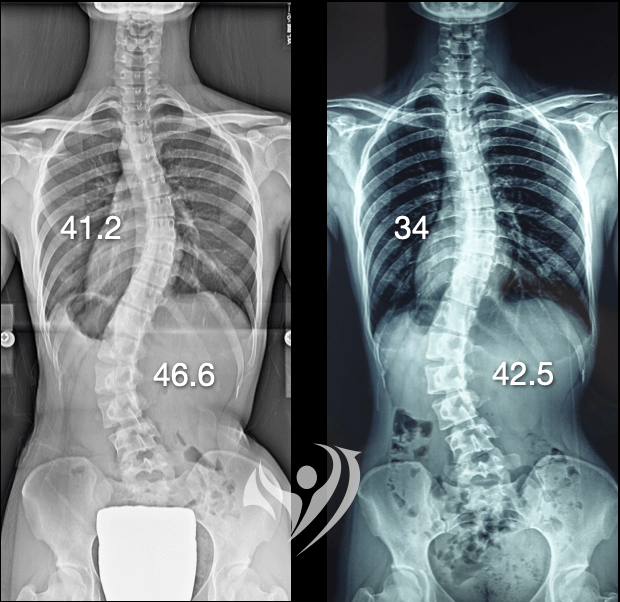

- 矯正背景: 高中時期(15-18 歲),原側彎度數約 40 多度。經 3 年每日 20 小時背架穿戴及密集矯正治療,度數一度改善至 20 多度。

- 反彈現況: 於 23 歲時追蹤,胸椎側彎惡化至 41.2°,腰椎側彎惡化至 46.6°,幾近回到最初彎曲程度。

✅ 成果:該個案以一週一次的低頻率學習,一年後追蹤結果:

- 胸椎側彎41.2°→34°

- 腰椎側彎46.6°→42.5°

結果表明,即使在成年後、訓練頻率不高,透過改變中樞神經的姿勢策略,側彎度數仍能獲得顯著改善。